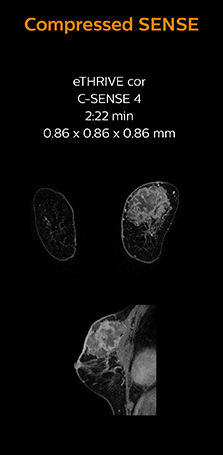

“Previously with SENSE, our 2D mDIXON TSE scans required relatively long scan times. But now, with Compressed SENSE, we have reduced these scan times while maintaining a high SNR, because the Compressed SENSE technology helps reduce noise,” says Dr. Koyama. “Because the faster scanning with Compressed SENSE saves us time, we can sometimes add a sequence to obtain high quality spine images in the same time slot for confident diagnoses. And in cervical spine exams, a 2D sequence is sometimes replaced by a 3D protocol, which provides us more information as it can be reformatted in different orientations. Compressed SENSE allows us to easily add this 3D sequence in the timeslot,” says Fukushima “Incorporating Compressed SENSE in common spine sequences, such as mDIXON, 3D SpineVIEW and eTHRIVE, can substantially reduce the scanning time of these sequences, while maintaining adequate spatial resolution, resulting in high quality, multiple contrasts, multiple orientations,” says Dr. Koyama. “In addition, fast sequences generally make it easier for patients to stay motionless throughout the scans, so it also helps us in that way.”

The KCH team has already changed most of their Ingenia 1.5T spine ExamCards by incorporating Compressed SENSE into their 2D TSE, mDIXON TSE, FFE, and 3D sequences.

This 6-year-old patient with neuroblastoma underwent MRI on the Ingenia 1.5T. Compressed SENSE was used to reduce scan time while maintaining the high resolution for 2D mDIXON, 3D SpineVIEW and e-THRIVE in this case. The highly detailed images allowed the radiologist to make a quick and confident assessment of the position of the nerve and the tumor. Especially important for a pediatric patient, is that a shorter scan time also allows us to keep the sedation time as short as possible.

As this was one of the first patients scanned with Compressed SENSE, 3D SpineVIEW was acquired with and without Compressed SENSE to allow comparison. Although the Compressed SENSE sequence was significantly faster, the acquired and reconstructed 3D SpineVIEW images show virtually the same image quality.